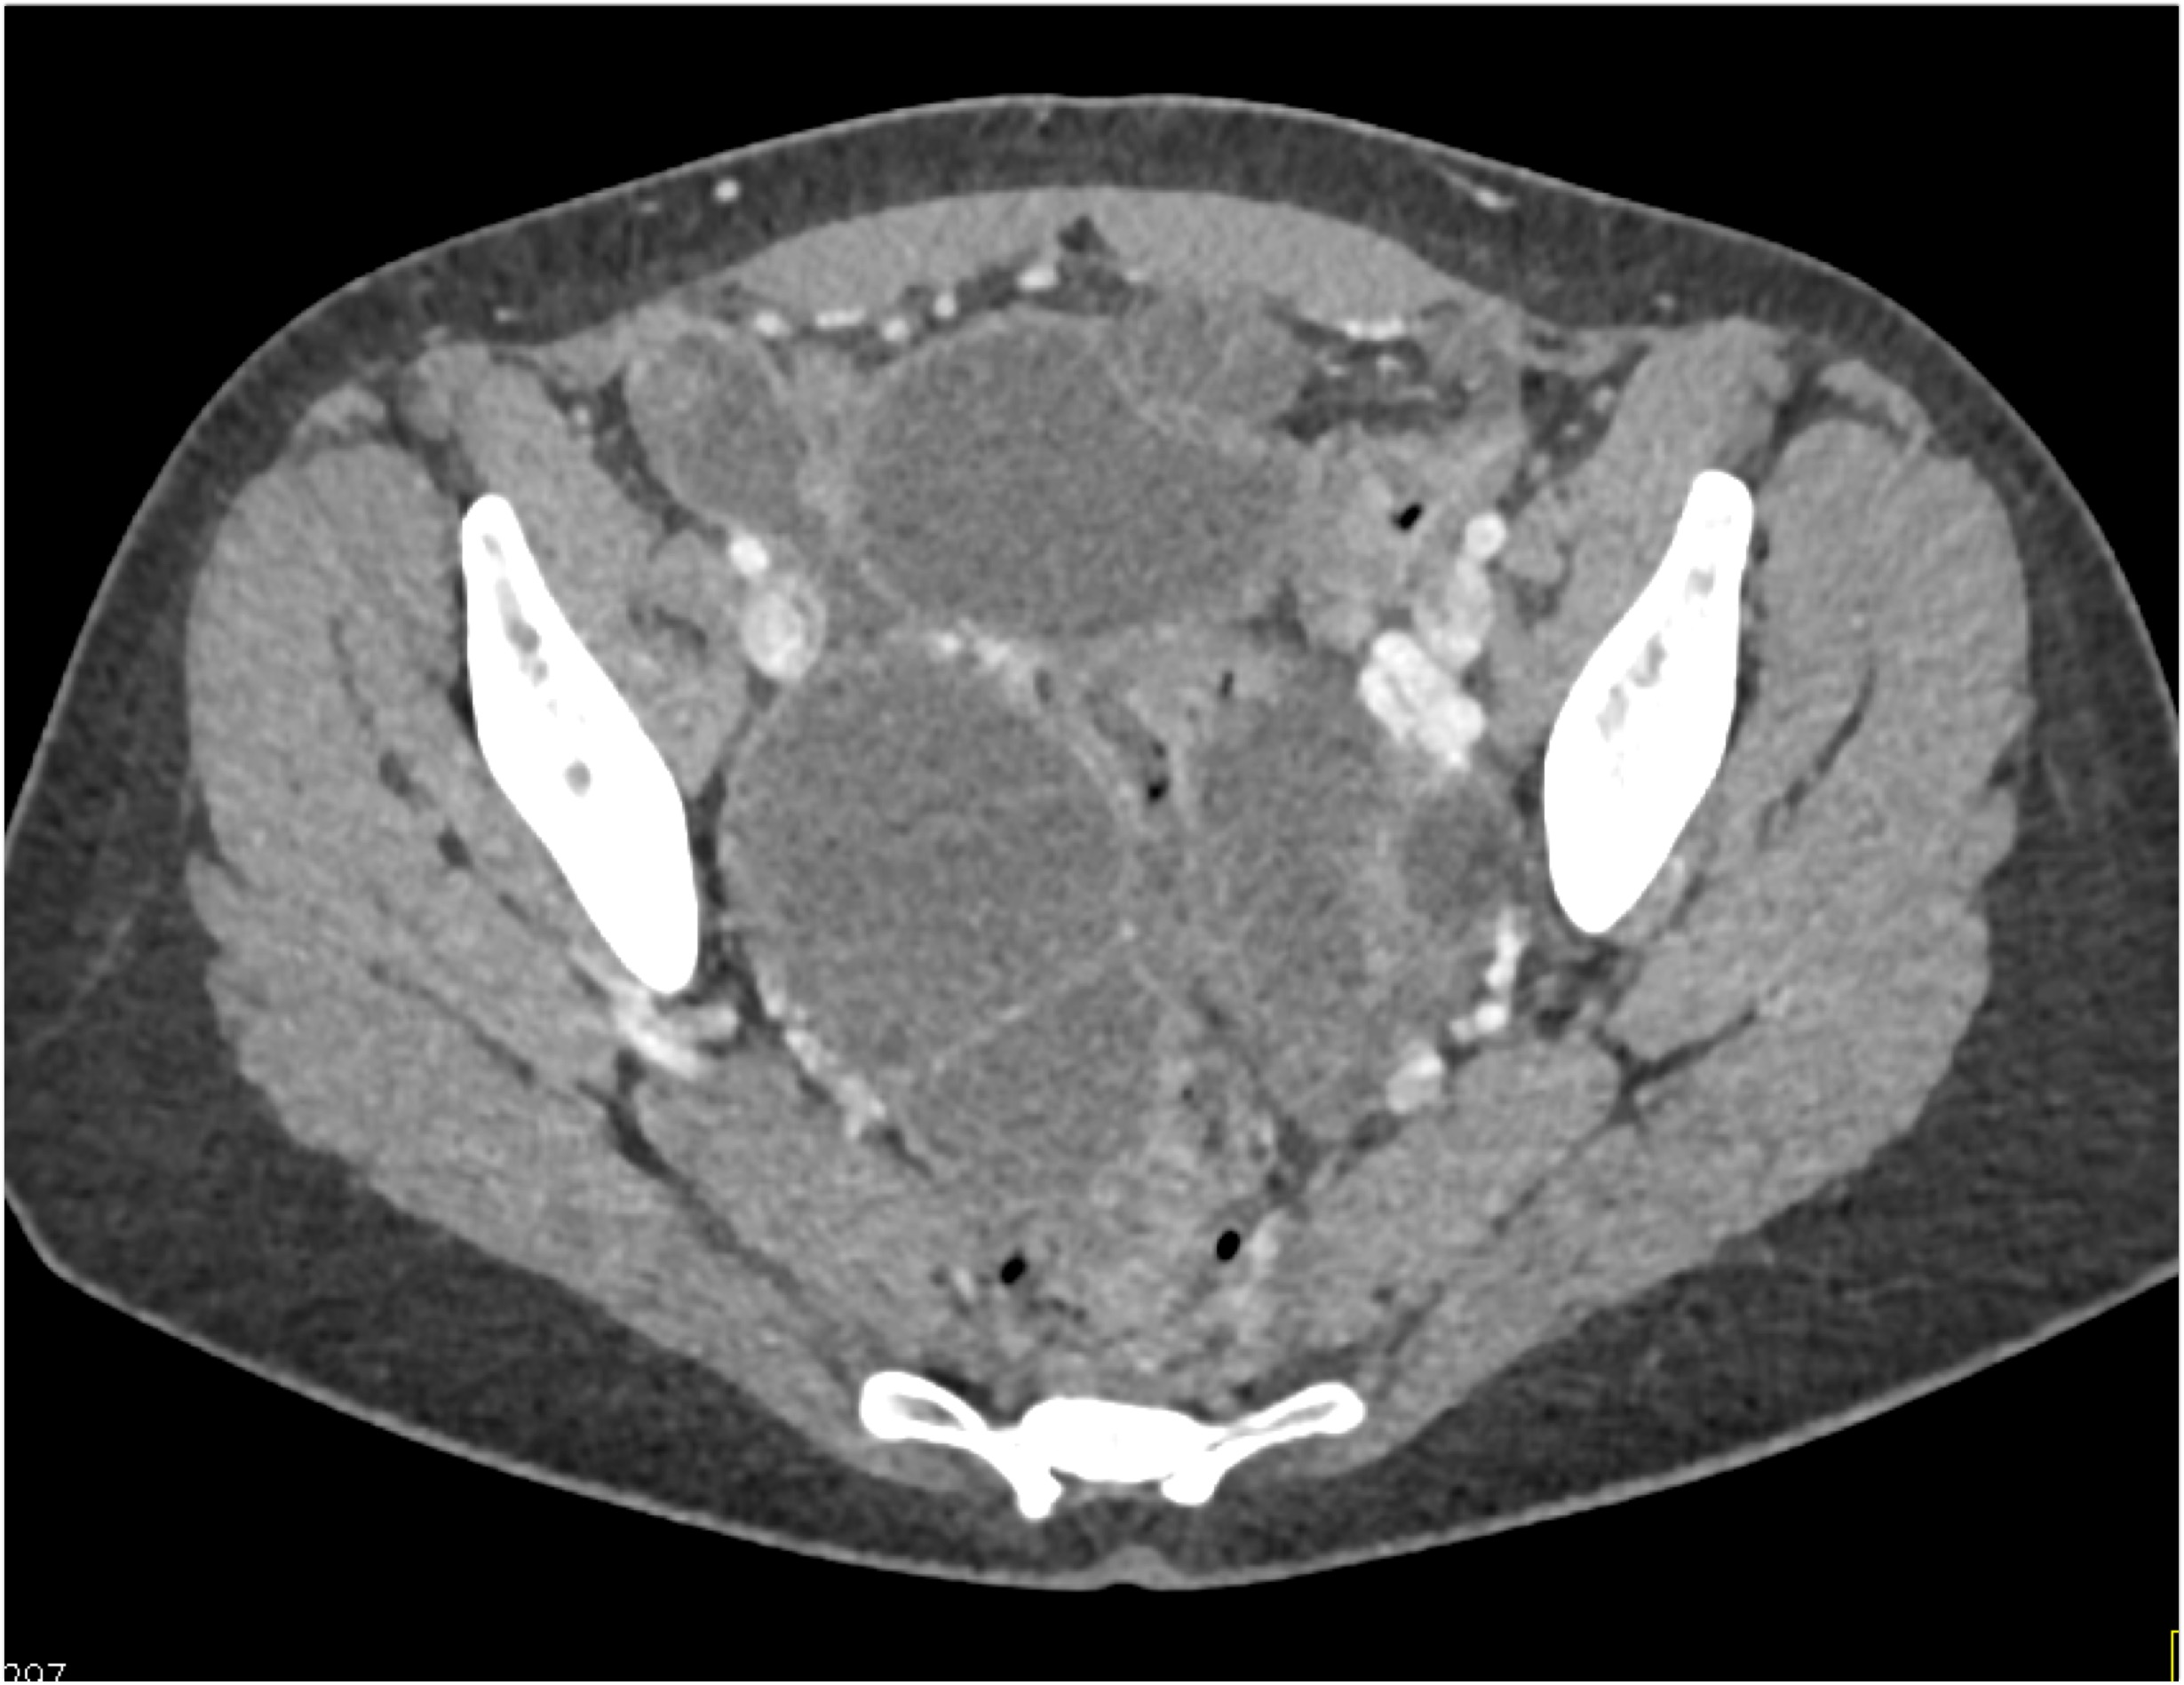

- Evaluate the CT images of each question carefully.